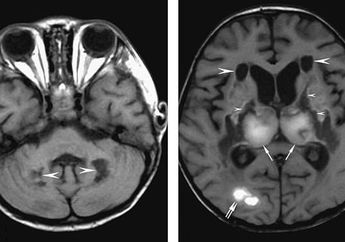

Penelitian Terbaru Menunjukkan bahwa Pasien Positif Corona juga Mengalami Kerusakan Otak yang Membuat Penderitanya Mengalami Hal Mengerikan Ini selama Hidupnya!

5 Tahun yang lalu - Terungkap, jika virus corona atau Covid-19 berdampak terhadap otak manusia. Diketahui, bikin pasien alami kerusakan otak atau pembengkakan otak.